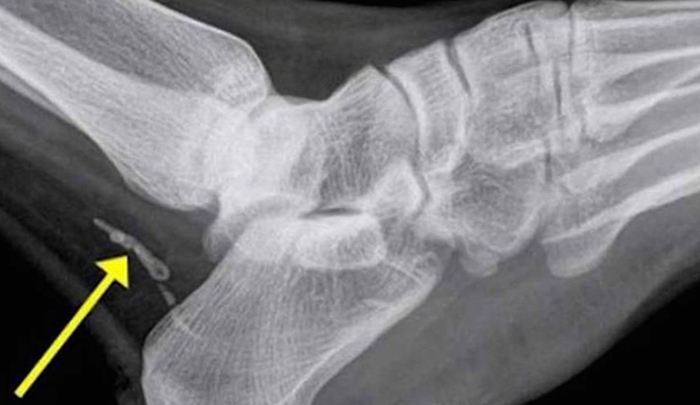

При изучении содержимого язвы под микроскопом обнаруживается большое количество личинок паразита. Рентгенодиагностика показывает хорошо видимые обызвествленные тела самок на пораженных участках; анализ крови позволяет оценить степень аллергических реакций в организме (увеличивается количество эозинофилов и антител).